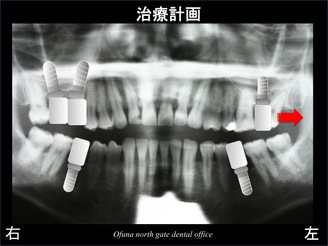

そこで、以下のような方法を行い、少しでも長いインプラントを埋入する治療計画を立てました。

1.インプラントを斜めに埋入することにより、

少しでも長いインプラントを埋入できるように

する!

これをインプラントの傾斜埋入と言います。

2.ソケットリフト法 を応用し、

少しでも長いインプラントを埋入する!

上記のような方法を組み合わせることにより以下のレントゲンのように治療を行う計画を立てました。

以下が最終的な治療計画になります。